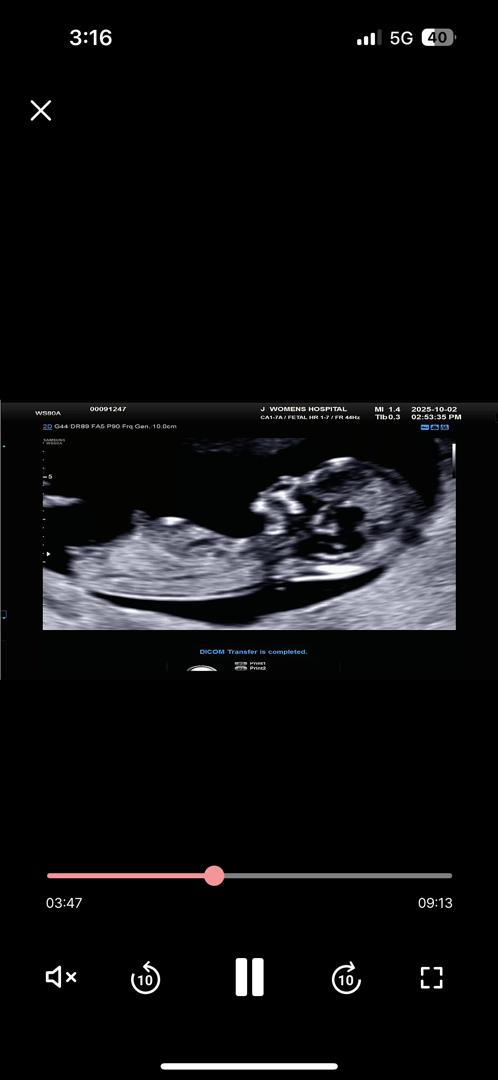

12주 각도법 성별 투표해주세요

두구두구